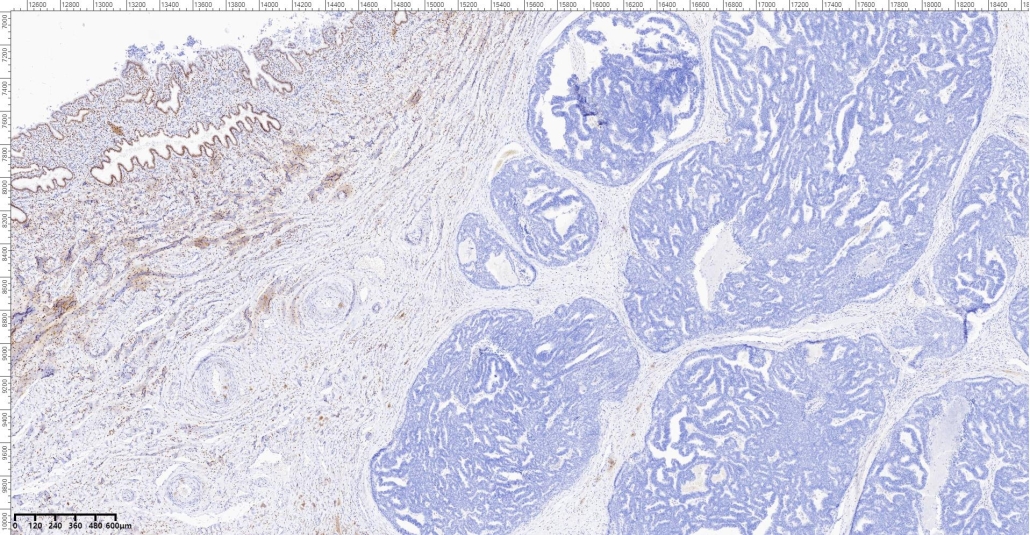

A 65-year- old female presented with vaginal bleeding. On radiological examination there was a diffuse thickening of endometrium. Patient underwent total abdominal hysterectomy and bilateral salpingo ophrectomy. On gross examination there was a grayish white mass involving the uterine cavity.